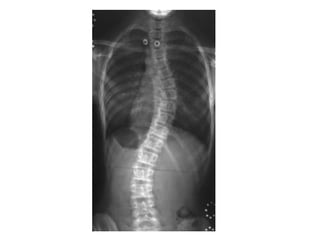

INCIDÊNCIAS ESCOLIOSE

COLUNA TOTAL ESCOLIOSE